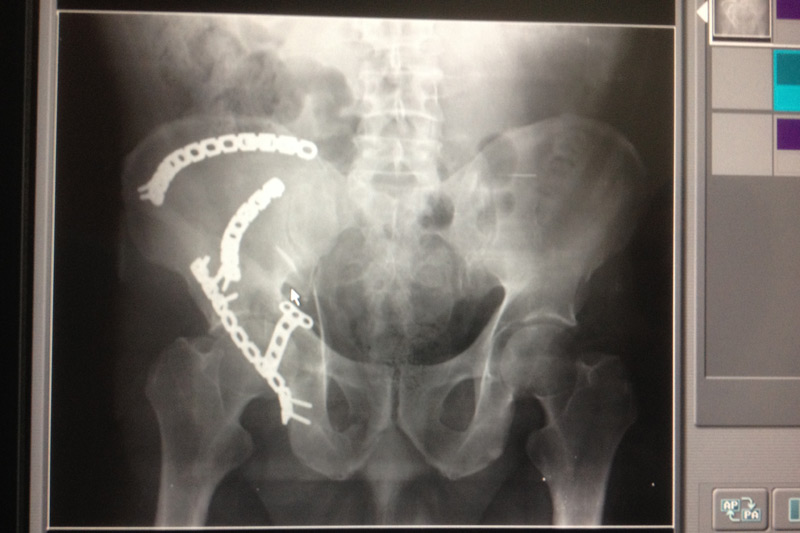

Dentro del avance en medicina se incluye la cirugía artroscópica, su característica es la mínima invasión, se realizan portales ( incisiones ) menores de 8 mm, por el cual se realizan cirugías ortopédicas con la finalidad de restaurar la congruencia articular, obteniendo excelentes resultados incluyendo ausencia de dolor y una pronta reincorporación a sus actividades cotidianas.